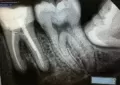

Болит десна под зубом (верхняя правая шестерка). Сделан снимок в частной клинике. Врач отказалась лечить, отправила на удаление. В городской стоматологии хирург переделал снимок, сказал, что не все так страшно, можно попить антибиотики и посмотреть уйдет ли инфекция. Прописал амоксициллин и супрастин.

Обезболивающие не справляются, десна очень болит. Задумываюсь уже пойти и просто вырвать, но очень жалко, если все-таки его можно спасти.

Оба врача говорят, что бесполезно вскрывать его. А может все-таки можно вскрыть и заложить туда лекарство?